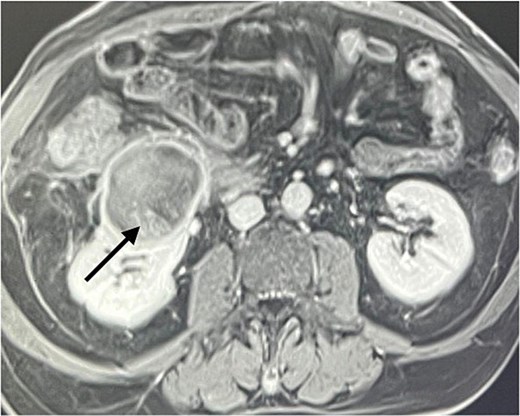

A 60-year-old male patient was referred to our clinic due to concern of infected renal cyst. Five months prior to referral, he underwent an open appendectomy and right limited hemicolectomy due to perforated appendix. At that time he was found to have accidental right Bosniak IIF renal cyst on CT scan and follow up every 6 months was recommended by urologist. Four months later, he came to emergency department with fever, chills and right flank pain. CT scan of the abdomen and pelvis with intravenous contrast was done and showed same size exophytic cyst in the lower portion of the right kidney measuring 4.9 × 5.2 cm but with new finding of rim enhancement with surrounding fat stranding suggesting complicated cyst with possible abscess formation. There was fat stranding and wall thickening of the adjacent ascending colon (Fig. 1). These findings couldn’t differentiate between infected cyst and cancer. Due to the high risk of malignancy associated with Bosniak IIF renal cyst and the challenging differential diagnosis, we further discussed the case with radiologist and decision was made to do an magnetic resonance imaging (MRI) with contrast for further evaluation and for better visualization of internal enhancement. Most MRI findings were suggestive of infected cyst. However, diffusion-weighted imaging and apparent diffusion coefficient (DWI-ADC) map showed strong internal restricted diffusion which is not specific to either abscess or tumor. Reaching the diagnosis based solely on these initial imaging findings was challenging. T1 post contrast image revealed fine internal enhancement suggesting more complex lesion than a simple infected renal cyst or abscess, raising suspicion for a neoplastic process (Figs 2 and 3).

An axial view (on the right) and sagittal view (on the left) showing a ring enhancing lower pole cyst (arrow), suggesting infected cyst vs abscess formation.